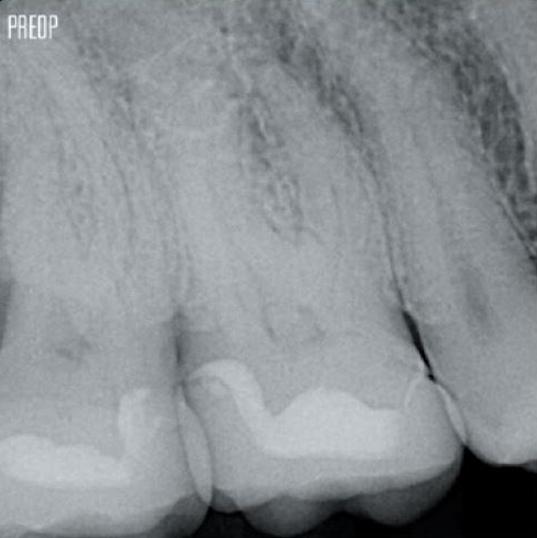

Photos courtesy of Dr. Ahmed Salman

More dentin preserved. Appropiate shaping, irrigation, and obturation ensured.

Successful root canal treatment starts with adequate access to the pulp chamber. The ideal procedure provides access to root canal orifices with minimal loss of dentin.

A Conservative Endodontic Cavity (CEC) is recommended with the TruNatomy® system.

The union of the file geometry, regressive tapers and the slim, highly-flexible wire enables efficient root canal treatment while removing only dentin where clinically needed.1